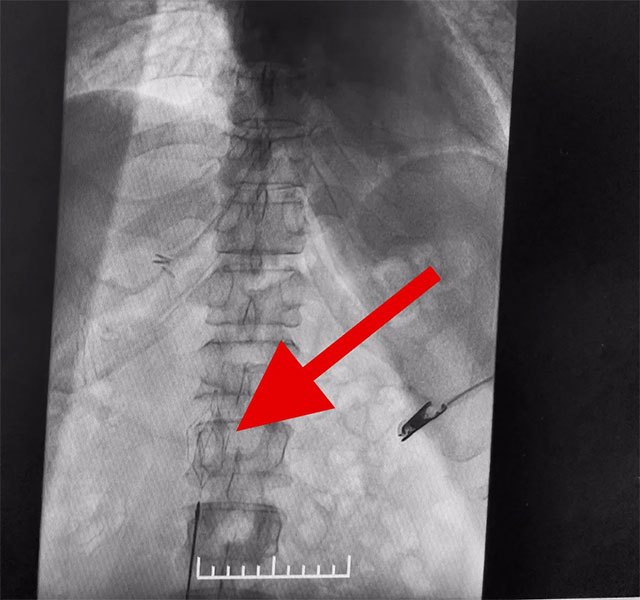

在征得家屬同意后,6月12日,張琪博士團隊為患者進行了下腔靜脈濾器置入手術。張琪博士在醫(yī)護團隊協(xié)助下將一個形似傘狀的人工濾器經患者右側股靜脈穿刺迅速置入下腔靜脈,“網”住了通往心血管和肺部的致命栓子,阻擋血液栓子進入肺動脈,及時挽救了患者生命。

▲ 下腔靜脈濾器置入成功